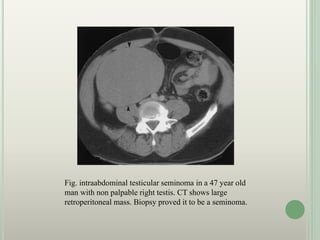

Fig. intraabdominal testicular seminoma in a 47 year old

man with non palpable right testis. CT shows large

retroperitoneal mass. Biopsy proved it to be a seminoma.